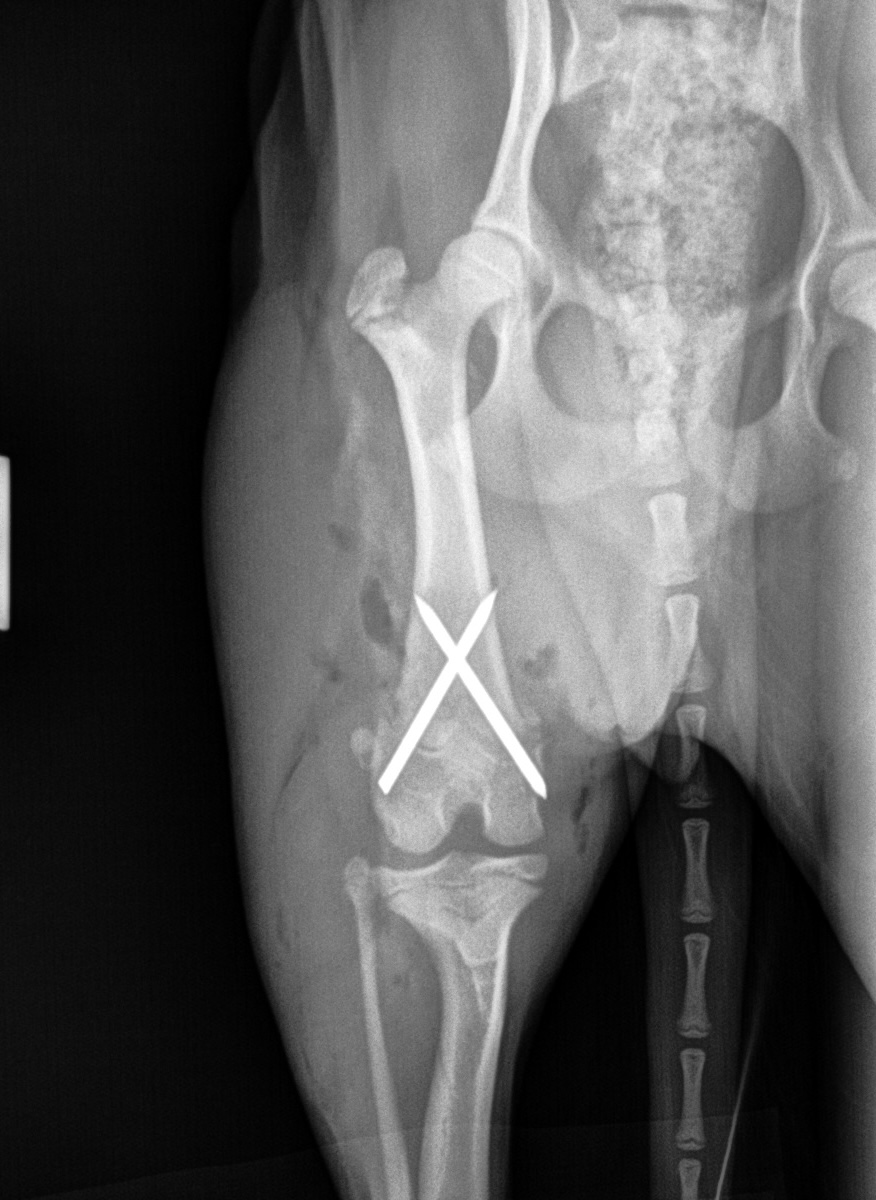

Femur Fracture Before

Femur Fracture After #1

Femur Fracture After #2